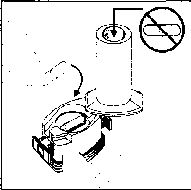

duymalısınız. Eğer bu vızıldama sesini duymazsanız, kapsül bölmesini açınız ve kapsülün, kapsül bölmesinde sıkışıp sıkışmadığını kontrol ediniz. Daha sonra 7. basamağı tekrarlayınız. Kapsülü sıkıştığı yerden kurtarmak için düğmelere tekrar BASMAYINIZ.

8. Cihazın içerisinden nefes aldıktan sonra, nefesinizi olabildiğince tutunuz ve cihazı ağızdan çıkarınız. Sonra burnunuzdan nefes veriniz. Kapsül bölmesini açınız ve kapsülde toz kalıp kalmadığını kontrol ediniz. Eğer kalmış ise 6-8. işlemleri tekrarlayınız

9. Tüm tozu kullandıktan sonra kapsül bölmesini açınız (Bkz. basamak 2). Boş kapsülü çıkarınız ve içeride kalan tozları temizlemek için kuru bir kağıt mendil ya da yumuşak bir fırça kullanınız.

Not: İnhalasyon cihazını temizlemek için SU KULLANMAYINIZ.

10. Önce ağızlığı, ardından kapağı kapatınız.

İlacınızı kullandıktan sonra ağzınızı suyla iyice çalkalayınız ve bu suyu tükürünüz. Bu işlem ağzınızda bir mantar enfeksiyonu (pamukçuk) gelişme olasılığını azaltacaktır.Değişik yaş grupları